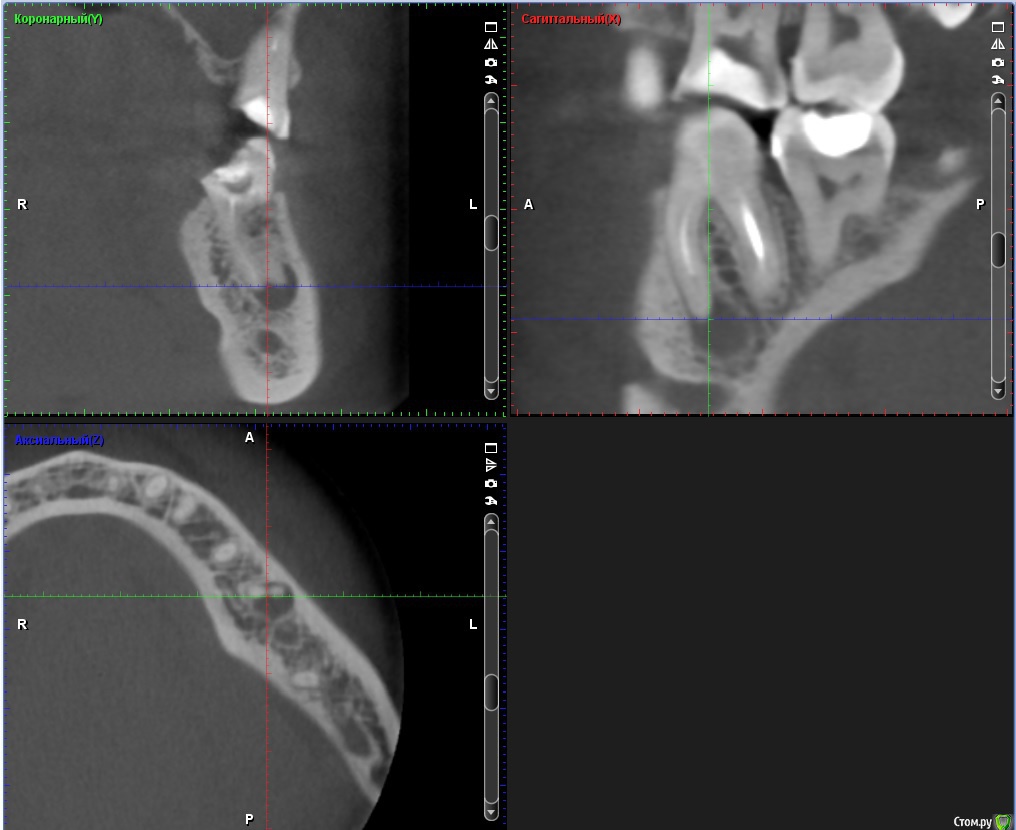

ClayMixer Опубликовано 18 ноября, 2016 Поделиться Опубликовано 18 ноября, 2016 (изменено) Здравствуйте! Вопросы по двум зубам (36 и 26): 1. Киста (36-ой зуб).Консультировалась у нескольких врачей. Мнения разные. От "можно поставить вкладку и коронку на n-ное количество времени до удаления; эту кисту не вылечить", до: "только удаление, желательно быстрее". 1) Можно ли вылечить этот зуб? И каков процент успеха?2) Есть ли смысл лечить зуб и ставить вкладку и коронку или лучше удалить и делать имплант? После того, как 36 зуб подготовили под вкладку - бывали неприятные непонятные ощущения (похожие на импульсы), не острые (длительностью 3 нед.) Вроде после этого времени стали утихать понемногу. 2. Инородное тело (обломок инструмента) в 26-м зубе.Врачи пытались извлечь его (без микроскопа) - безуспешно. Канал, в котором "застрял" инструмент не до конца "пройден".Критично ли это? Какова вероятность воспаления? (теперь патологический страх появления кисты ) Теоретически можно ставить вкладку и коронку? Ходила таким трансформером больше 5-ти лет, не беспокоил вообще. После попыток врачей достать инструмент также бывали неприятные непонятные ощущения (похожие на импульсы), не острые (длительностью 3 нед.) Вроде после этого времени стали утихать. При простукивании коронки обеих зубов болевых ощущений вроде не наблюдалось. Результаты КТ https://cloud.mail.ru/public/Fhy4/ESmeyU9hp Изменено 18 ноября, 2016 пользователем ClayMixer Ссылка на комментарий

ClayMixer Опубликовано 18 ноября, 2016 Автор Поделиться Опубликовано 18 ноября, 2016 26-ой зуб Ссылка на комментарий